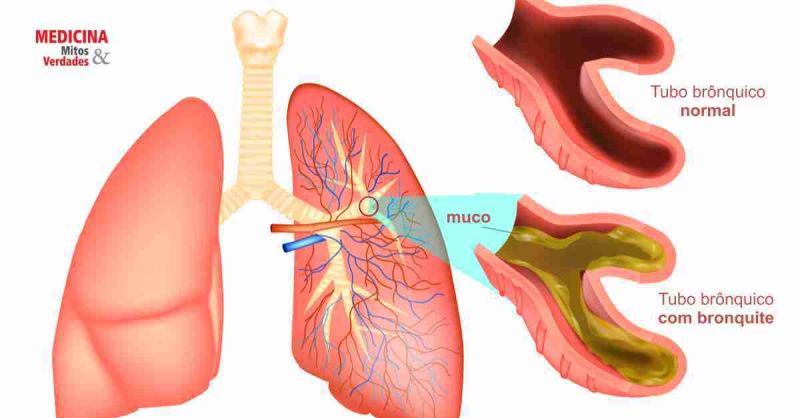

A bronquite é a inflamação dos brônquios, os tubos que levam ar aos seus pulmões. Sabe quando a gente tosse muito, sente o peito apertado e às vezes até sai catarro? Isso pode ser bronquite. Ela pode ser aguda, durando poucas semanas, ou crônica, persistindo por meses ou anos. A forma crônica está ligada a fatores como o cigarro, o que prejudica a função pulmonar e a qualidade de vida.

Identificar a bronquite cedo faz toda a diferença no tratamento. Quando inflama, a passagem de ar fica mais difícil, e o corpo reage com tosse para tentar limpar as vias aéreas. Se você sente esses sintomas com frequência, é essencial procurar um médico. Ele vai te orientar sobre a melhor forma de cuidar da sua saúde respiratória e evitar complicações.

Para quem não sabe, a bronquite inflama os brônquios, que são os “tubos” por onde o ar passa para chegar aos pulmões. Essa inflamação causa tosse, chiado e, às vezes, falta de ar. O vapor, por ser morno e úmido, acalma essa irritação nas mucosas. Ele hidrata a garganta e os brônquios, diminuindo aquela sensação de arranhão e o reflexo da tosse seca e persistente. É como dar um banho de hidratação por dentro, sabe?